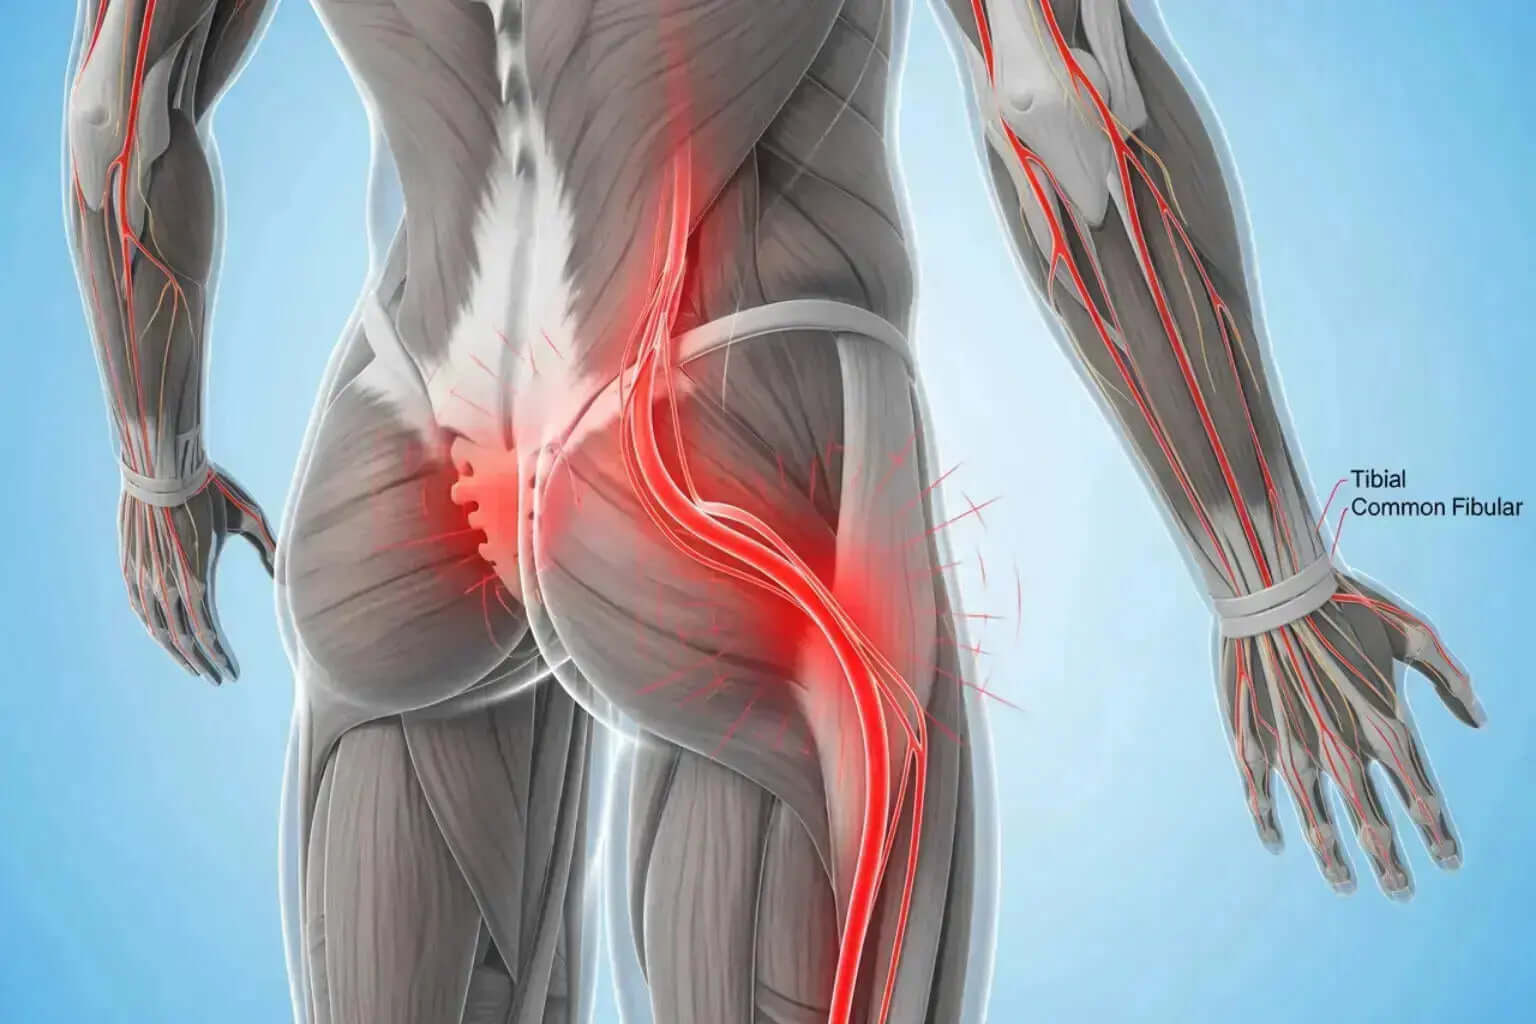

From sore muscles to nerve discomfort, we break down causes

and share expert-backed relief strategies.

A – Z Guide to What Causes Sciatica